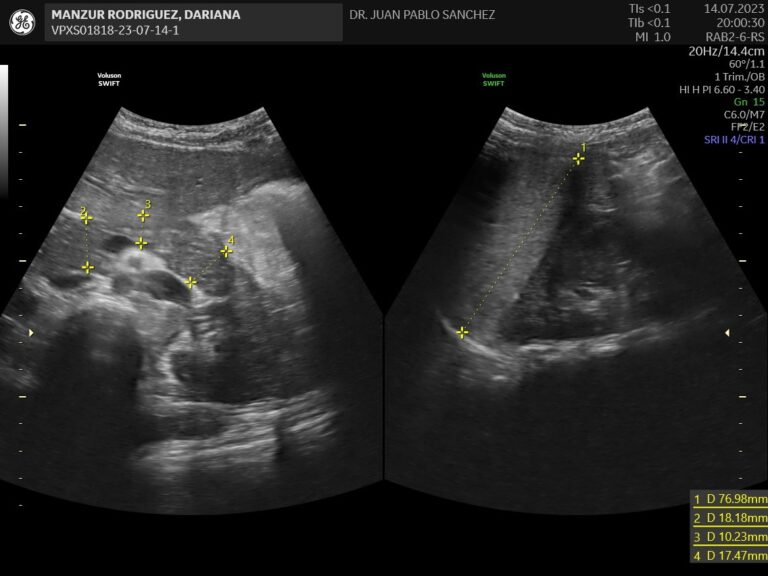

Ecografia abdominal

Estudio no invasivo que permite observar los órganos del abdomen, como el hígado, riñones, intestinos, vejiga, etc. Es útil para detectar infecciones, malformaciones o dolores sin usar radiación ni dolor.